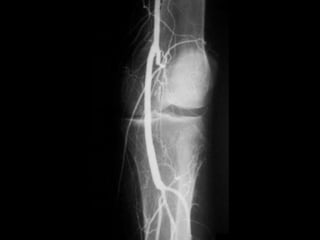

Observe

*Affection

from distal to

proximal.

*Pruning of

tibial vessels

and foot arch.

Clinical features: 1.Usually Youngmale 2. Heavy smoker 3. Migratory thrombophlebitis 4. ± Raynaud’s phenomenon

• 86.

• 88.